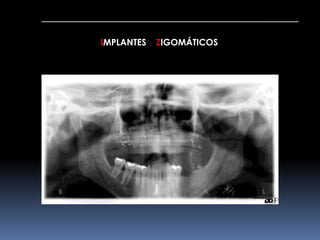

IMPLANTES ZIGOMÁTICOS     INDICAÇÕESMaxilar Edéntulo com Grande Reabsorção óssea		Pneumatização do Seio Maxilar	Status Pós-Maxilectomia	Fenda Lábio-Palatina